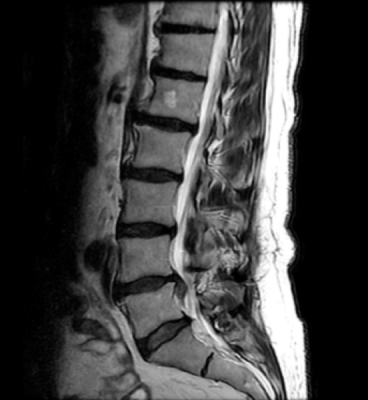

Subtle Medical's software solution, SubtlePET, uses proprietary deep learning algorithms to denoise low count PET images from up to 75% lower radiotracer dose and faster scan times. SubtleMR uses increased sharpness and denoising to improve the image quality on up to 60% faster MRI exams. Subtle's solutions are compatible across all PET and MRI scanner brands, makes, and models, and seamlessly integrate into existing workflows.